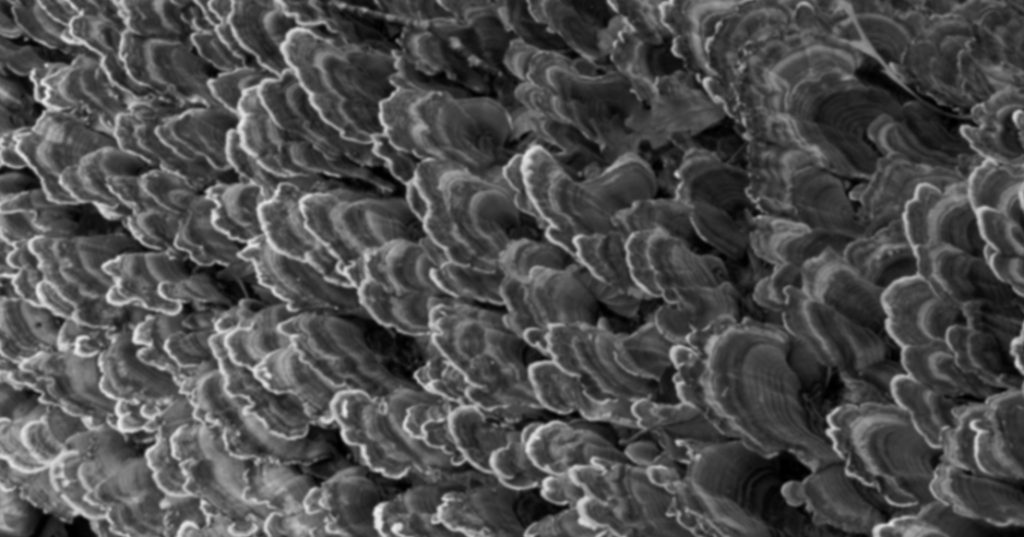

Erosion

While dietary acid is a source of erosion, it is certainly not the only one. Intrinsic acids (gastric acid) are a common source of erosion. Patients should be screened for a history of GERD, bulimia nervosa, and hiatal hernias. Interestingly, proteolytic enzymes, which are known to degrade the dentinal organic matrix, can be released into the oral cavity during vomiting (3). These enzymes arise from the stomach and pancreas and can also be found in gingival crevicular fluid (4).

Friction (Abrasion)

Abrasion (or friction) occurs when teeth are introduced to a foreign object that introduces a destructive mechanical force. The greatest offenders are applying excessive force when brushing teeth, using abrasive toothpaste, and using a horizontal brushing technique. Individuals with a thin tissue phenotype (formerly called biotype) are particularly susceptible to recession, which will more easily give way to abrasion (11). Other risk factors include the frequency and duration of the applied force. Clinical and lab data contend that there is little evidence that NCCLs are solely caused by abrasion (10).

The traditional abfraction theory postulates that upon occlusal loading, the cervical area of the tooth becomes a fulcrum. This action leads to tensile stress which leads to disruption of the enamel’s brittle crystalline structure. Repeated loading eventually causes enamel to break away from the margin (12).